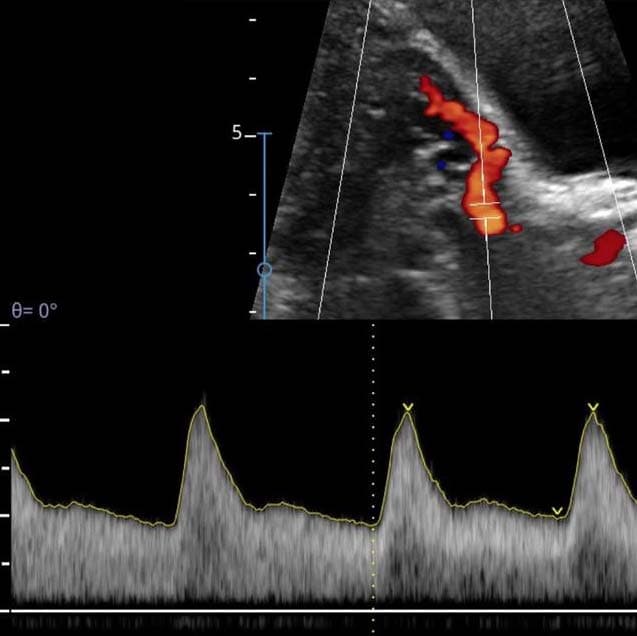

Ultrasonido Doppler

El ultrasonido Doppler a su vez tiene sus modalidades que son: Doppler Color, Doppler Poder y Doppler pulsado. La mayoría de ellos utilizados para la evaluación de los vasos sanguíneos y el comportamiento de su flujo, ya sean arterias o venas.